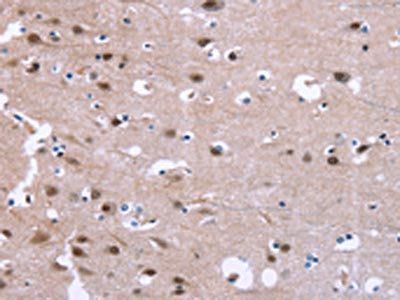

The image on the left is immunohistochemistry of paraffin-embedded Human brain tissue using CSB-PA257590(GPR171 Antibody) at dilution 1/25, on the right is treated with synthetic peptide. (Original magnification: ×200)